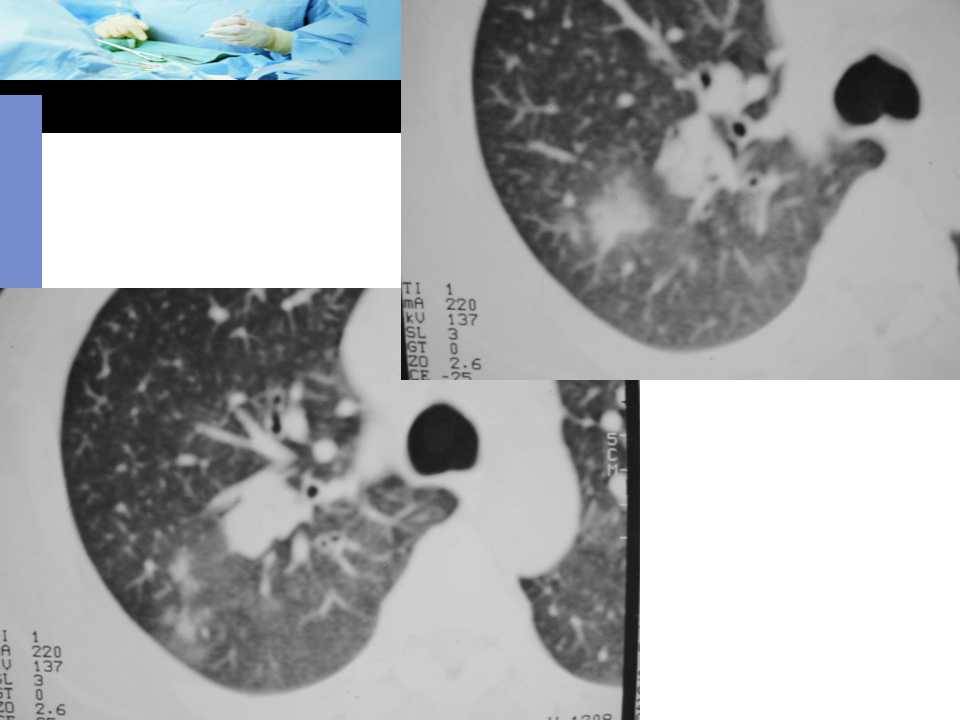

肺癌影像诊断